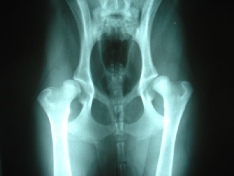

Hip Dysplasia

A brief overview as to why we 'Hip Score' German Shepherd Dogs before we breed.

Dog hip dysplasia is a common skeletal developmental problem generally found in larger dogs and, in particular, in  working and sporting dog breeds.  Dog hip dysplasia occurs because the upper ball portion of the dog's hind legs doesn't fit properly into the hip socket, causing instability within the ball-and-socket joint, which in turn eventually causes the hip bone to tear apart thus being called dog hip dysplasia.

At this point in time, no one knows exactly what causes dog hip dysplasia, but most vets now agree that dog hip dysplasia is probably an inherited condition. They also agree that the dog hip dysplasia probably isn't influenced by a dog's diet, although dog hip dysplasia is aggravated by excessive weight and obesity problems. They suspect that the animal's overall weight and/or very rapid growth during puppy hood may be contributing factors for dog hip dysplasia.

The current BVA/KC scoring scheme for hip dysplasia (HD) has been in operation since 1984 and since then over 100,000 X-rays have been assessed. Dysplasia means abnormal development, and the degree of hip dysplasia present is indicated by a score assigned to each hip. The hip score is the sum of the points awarded for each of nine aspects of the X-rays of both hip joints. The minimum hip score is 0 and the maximum is 106 (53 for each hip).

The lower the score the less the degree of hip dysplasia present.

An average (or mean) score is calculated for all breeds scored under the scheme and advice for breeders is to use only breeding stock with scores well below the breed mean score.